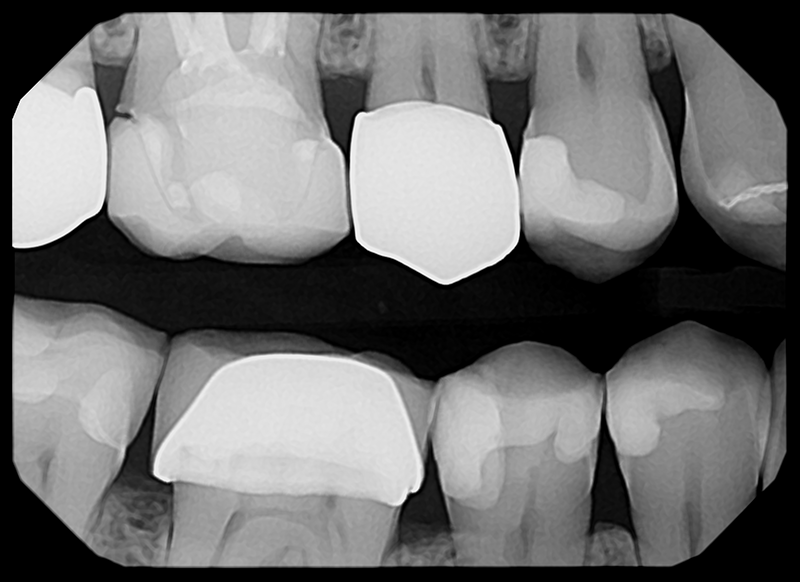

Crisp Images, Low Exposure

The low-noise design delivers exceptional clarity even at lower doses. Keeps patients safer while improving diagnostic confidence.

0.145 s

Capture Every Detail — High-Quality Imaging. Designed for Patient Comfort.

See The Clarity For Yourself